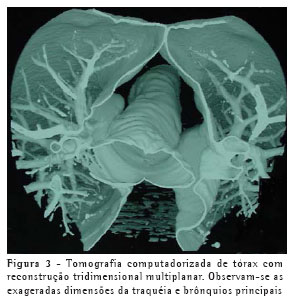

Um paciente do sexo masculino, de 40 anos, cor negra, foi encaminhado ao ambulatório de pneumologia por fadiga aos esforços e tosse seca persistente, três semanas após ter recebido alta de uma internação hospitalar para tratamento de uma pneumonia. Havia apresentado, 40 dias antes, febre de início súbito, tosse produtiva com hemoptise de pequena quantidade (raias), e dispnéia. Recebeu o diagnóstico de pneumonia e foi internado, tendo recebido cefazolina intravenosa por sete dias, com boa evolução. Referia ainda três episódios prévios de pneumonia, o primeiro quando com 22 anos de idade. O radiograma de tórax realizado no momento da avaliação evidenciava consolidações discretas no lobo médio, de aspecto residual, além de aumento importante do diâmetro traqueal e dos brônquios principais. Realizou tratamento empírico com broncodilatador, sem resultado, por duas semanas, quando então retornou para reavaliação. A tosse havia piorado e passou a ser produtiva. O radiograma de tórax neste momento evidenciou novas consolidações, em ambos os lobos inferiores e no lobo médio. Não havia alteração nos sinais vitais e o paciente encontrava-se em bom estado geral. Recebeu prescrição de eritromicina via oral por dez dias. Nos primeiros três dias houve melhora da tosse e da fadiga e, ao final dos dez dias, a tosse havia melhorado quase completamente.

Poucos dias após o término do curso do tratamento com eritromicina, entretanto, o paciente voltou a apresentar tosse produtiva, associada a febre, e o radiograma não evidenciou melhora das consolidações. Foi novamente internado e realizou-se bacterioscopia de escarro, que evidenciou inúmeros polimorfonucleares e cocos gram-positivos em abundância. Cultura não era disponível. Iniciou tratamento com oxacilina intravenosa, obtendo resposta clínica satisfatória em poucos dias, motivo pelo qual foi iniciada a administração de cefalexina por via oral. Voltou a apresentar febre após 48h de uso de cefalexina via oral, o que motivou retorno para tratamento intravenoso e transferência para hospital de maior complexidade para investigação etiológica mais elaborada. O novo exame bacterioscópico de escarro neste momento evidenciou flora polimicrobiana e o paciente iniciou o uso de ceftriaxona associada a amicacina, com duração total de quatro semanas de tratamento, até a total resolução dos sintomas. Neste momento, foi realizada uma tomografia computadorizada de tórax, que demonstrou persistência das lesões consolidativas, de menor tamanho, em ambos os lobos inferiores, e confirmou o alargamento anormal da traquéia e brônquios principais (Figuras 1, 2 e 3), com bronquiectasias cilíndricas bilaterais nos lobos inferiores, caracterizando o diagnóstico de traqueobroncomegalia congênita, ou síndrome de Mounier-Kühn. As provas de função pulmonar evidenciaram aumento da capacidade pulmonar total (123% do previsto) e do volume residual (160% do previsto), sem outras alterações.

O diagnóstico pode geralmente ser feito utilizando-se apenas dados provenientes da radiologia convencional de tórax, através da mensuração do diâmetro traqueal, melhor visualizado na projeção em perfil. A tomografia computadorizada de tórax, entretanto, torna mais precisa essa mensuração. Os limites são 3 cm para diâmetro transverso da traquéia, e 2,4 cm e 2,3 cm para os diâmetros transversos dos brônquios principais direito e esquerdo, respectivamente. As provas de função pulmonar demonstram tipicamente aumento da capacidade pulmonar total à custa do volume residual, eventualmente com sinais de distúrbio ventilatório obstrutivo. Inexistem atualmente tratamentos específicos para esta condição além de antibioticoterapia durante as exacerbações e fisioterapia visando a auxiliar a eliminação de secreções, se houver. A utilização de próteses definitivas é reservada apenas para casos avançados selecionados, pois não existem indicações precisas.(5-6)